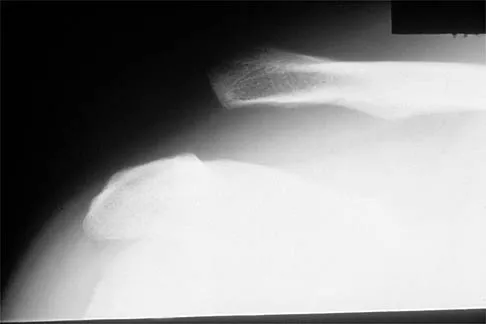

Figure 17 shows the radiograph of a 25-year-old professional football player who has superior shoulder pain that prevents him from sports participation. History reveals that he sustained a shoulder injury that was treated with closed reduction and temporary pinning 3 years ago. The best course of action should be

Explanation